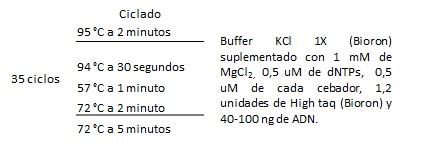

Se realizaron PCR con cada par de oligonucleótidos utilizando los genomas extraídos de la cepa silvestre. Los cebadores utilizados para la detección de las especies bacterianas A. actinomycetemcomitans, P. gingivalis, P. intermedia, T. forsythia y F. nucleatum fueron los que se muestran en la Tabla 1. Las condiciones de las PCR multiplex para la detección de estos microorganismos se muestran en las Tablas 2 y 3.

Tabla 3: Condiciones de la PCR multiplex para la detección de P. gingivalis, P. intermedia, A. actinomycetemcomitans

La visualización de los resultados de las amplificaciones (bandas) se realizaron en geles de agarosa al 1.2%, buffer TBE (Tris-borato-EDTA) 0.5x, 5µl de GoodView, 2µl de cyan/orangeloading buffer; 2-5 µl del producto del PCR durante 2h a 80V; y fotografiados con una cámara digital colocada encima de un transiluminador con luz ultravioleta (UV) (Figs. 4 y 5).